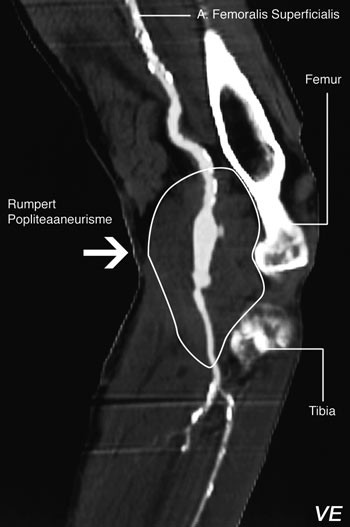

En 77 år gammel mann var gjennom en 12-årsperiode operert for aneurismer på bukaorta, bekkenarterier og arterier i lysker og knehaser. Han ble innlagt med dyp venetrombose i venstre lår og behandlet med warfarin. På grunn av økende hevelse og smerter i låret ble han overflyttet til Aker universitetssykehus 20 dager etter at symptomene debuterte. Etter ytterligere tre dagerble han operert med incisjon og evakuering av 800 ml illeluktende, brunfarget puss og nekrotisk vev. Vi fant også et rumpert aneurisme på venstre a. poplitea (fig 1). På høyre side var det likeledes et aneurisme, men det var ikke rumpert (fig 2). Infisert femoropopliteal bypass ble fjernet og erstattet med en ny bypass under kneleddet med snudd autolog vene.

På dag 17 ble det foretatt sirkulasjonsfysiologisk utredning. Dupleksundersøkelse viste et rumpert popliteaaneurisme med blødning ut av aneurismesekken på venstre side.

Selv ved ultralyd, dupleks og CT kan man feiltolke funnene og derved overse et rumpert popliteaaneurisme (1, 2). De anatomiske forholdene og strukturene rundt kneleddet begrenser størrelsen på hematomet, og pasienten får sjelden livstruende blødninger.